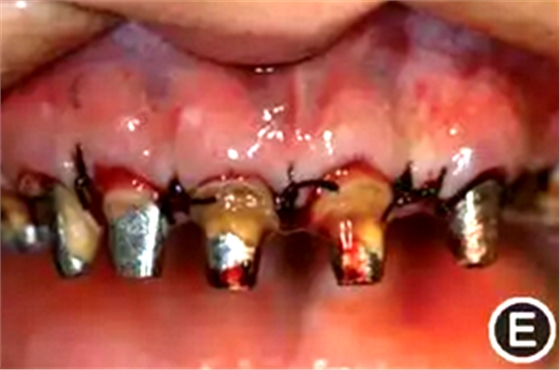

圖5 有利于健康、功能及美學效果的牙冠延長術手術過程 A:戴入手術導板;B:在手術導板的指導下確定手術切口;C:翻瓣后可見唇側骨板肥厚、形態(tài)不佳,上前牙鄰面及唇側原有肩臺距離骨嵴頂≤ 2 mm,侵犯了生物學寬度;D:骨切除及骨成形后唇側骨板形態(tài),肩臺距牙槽嵴頂約4 mm;E:齦瓣復位縫合,原有肩臺均位于齦上